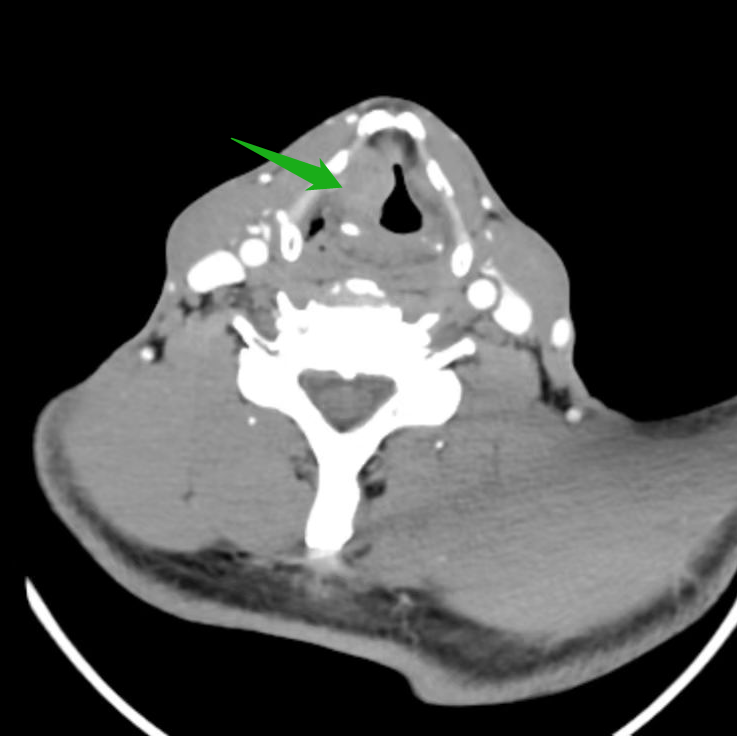

医生考虑喉新生物为恶性肿瘤,已经到了中晚期,建议先活检,再全喉切除。但张大叔平日里喜欢与朋友畅谈,不肯切全喉,家里的亲戚轮番来劝。耳鼻咽喉头颈外科刘蓉蓉主任、姬长友教授接诊后,立刻完善颈部 CT,显示 1. 右侧室带及声带增厚伴软组织结节形成,考虑新生物,建议病理组织学检查 2. 颈部少许小淋巴结。

取右侧声带病变组织活检,证实了喉癌的判断。考虑到喉癌范围极大,右侧声带已经固定,建议张大叔全喉切除。但其仍「意志坚定」,坚决不切全喉。刘蓉蓉主任、姬长友教授详细研究,制定了把右喉体及右侧甲状软骨板「连锅端」,保留左侧喉组织的方案,既可以彻底解决问题,又照顾到张大叔关于保留喉功能的顾虑。